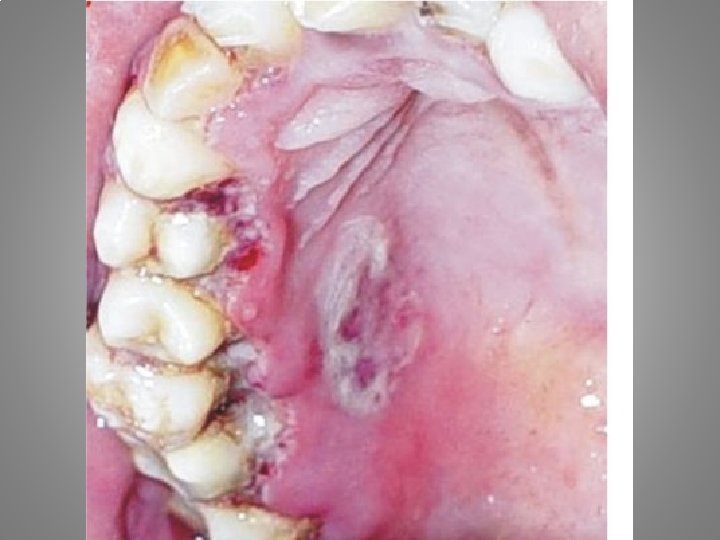

Types of orofacial pain Odontalgia : - Exposed dentin - Caries - Pulpitis - Apical periodontitis - Craced tooth sy. - Occlusal trauma - Periodontal abscessacute necrotising gingivitis - Periodontitis

• 19 years old male. A few days earlier started the pain in the submandibular area. The intraoral examination show out the edema, and erythema of the oral mucosa around 47 region. Dg. Th.